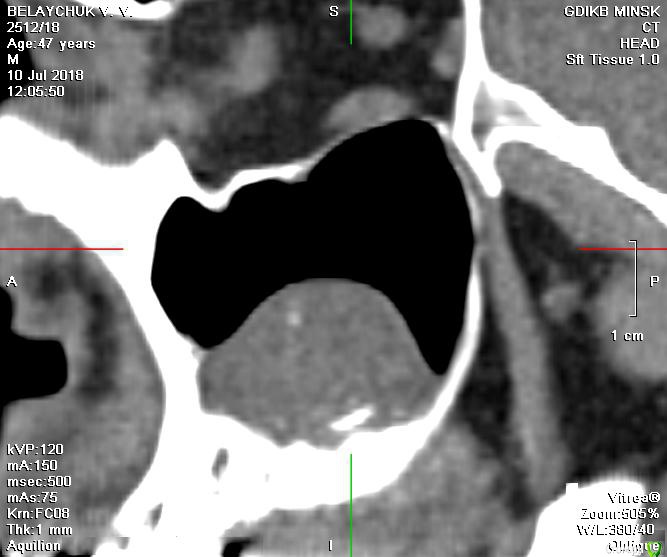

V20 Опубликовано 28 апреля, 2019 Поделиться Опубликовано 28 апреля, 2019 (изменено) Доброго времени суток , помогите пожалуйста разобраться с ситуацией.В мае 2018 года был проведен синус лифтинг с одновременной установкой 3 имплантов, Спустя 5-7 дней на фоне приема антибиотиков(Аугментин), развился левосторонний гайморит. Прошел курс консервативного лечения, пазуха успокоилась.Было решено протезироваться . В феврале 2019 года при откручивании ФД выкрутился имплант (по центру ) и образовался свищ, . Была сделана пластика свища. Сообщение закрылось.На настоящий момент сохраняется чуть заметная припухлость щеки в проекции пазухи и немного поднывает десна.(больше в районе крайнего импланта) На ощупь языком в месте соприкосновения десны и щеки небольшая припухлость ( похоже по проекции разреза).Что интересно с утра десна не болит начинается дискомфорт чуть позже. Уважаемые доктора , помогите пожалуйста в дальнейшей тактике - мнения врачей кардинально расходятся(снимки через неделю после синус лифтинга Снимок 3 месяца назад после консервативного лечения у ЛОРа Последний снимок (2 месяца назад) И еще хотелось бы услышать Ваше мнение о импланте на месте 24 зуба Заранее спасибо. Изменено 28 апреля, 2019 пользователем V20 Ссылка на комментарий

Bier Опубликовано 29 апреля, 2019 Поделиться Опубликовано 29 апреля, 2019 сейчас там синусит, я бы влез туда, посмотрел. Ссылка на комментарий

Bier Опубликовано 1 мая, 2019 Поделиться Опубликовано 1 мая, 2019 Я бы раскрыл как при синуслифтинге, чтобы оценить что там такое. По КТ все не очень хорошо. Ссылка на комментарий